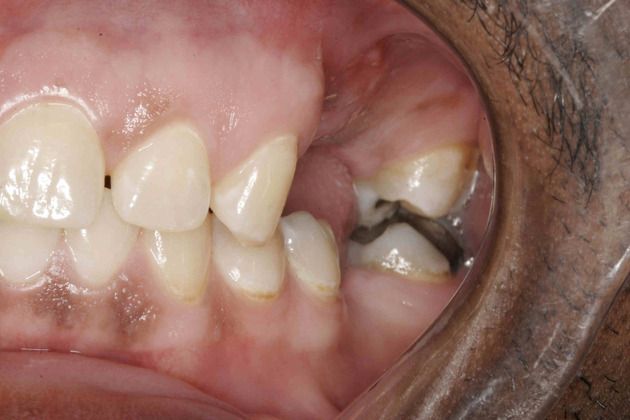

This patient was uncomfortable with his smile and the condition of his teeth. He had many cavities and had lost some teeth. He was very uncomfortable in the dental office and had let his mouth deteriorate. He wanted a healthy mouth and a nicer smile. IV sedation was utilized to make his appointments totally comfortable. Using dental implants to replace his missing or hopeless teeth and porcelain crowns and veneers, his mouth was transformed. The result was a healthy and fantastic new smile.